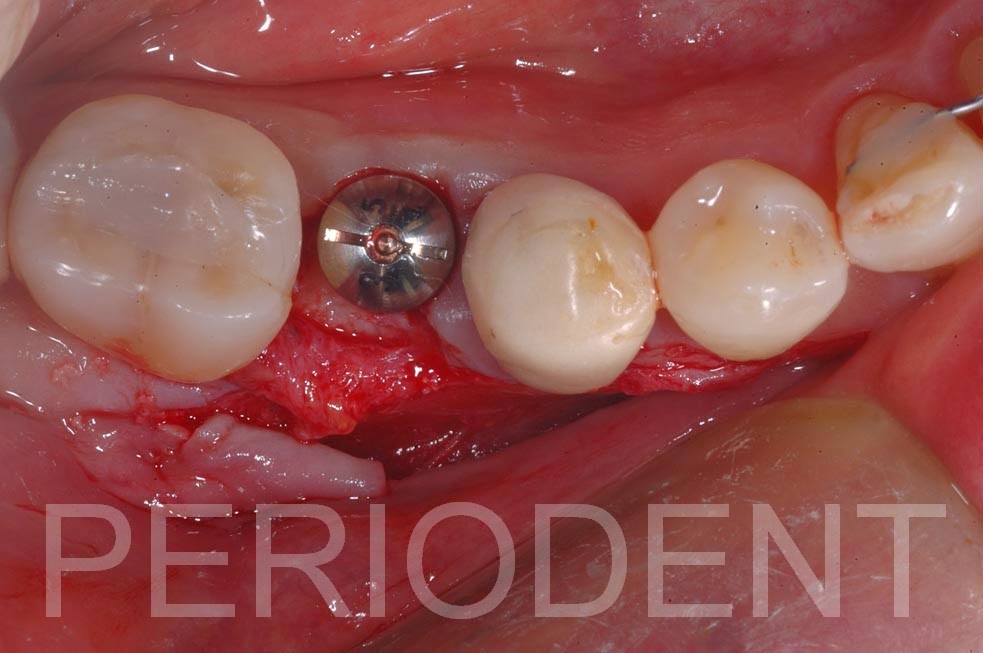

矯正治療結束後,第二小臼齒進行植牙,並同時補角化牙齦

拆線時